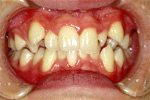

| 治療前 |